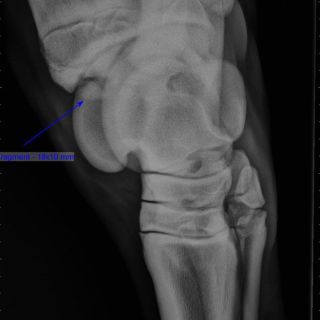

Radiologie (digital)

• Lahmheitsdiagnostik

Orthopädie